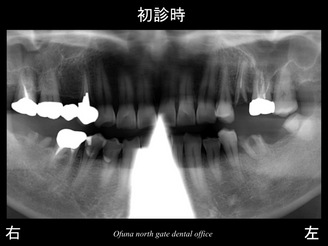

それでは初診時のレントゲンから見てみましょう。

右下の奥歯と左下の奥歯の被せ物が取れてしまったため、

『奥歯で物が噛めない!』との問題から当医院を受診されました。

診査をすると被せ物が取れた歯は、虫歯が非常に深い状態でした。

上顎の左側の奥歯も被せ物が取れている状態でした。

これらの歯は神経がない歯です。

以下の青丸:●が神経がない歯です。